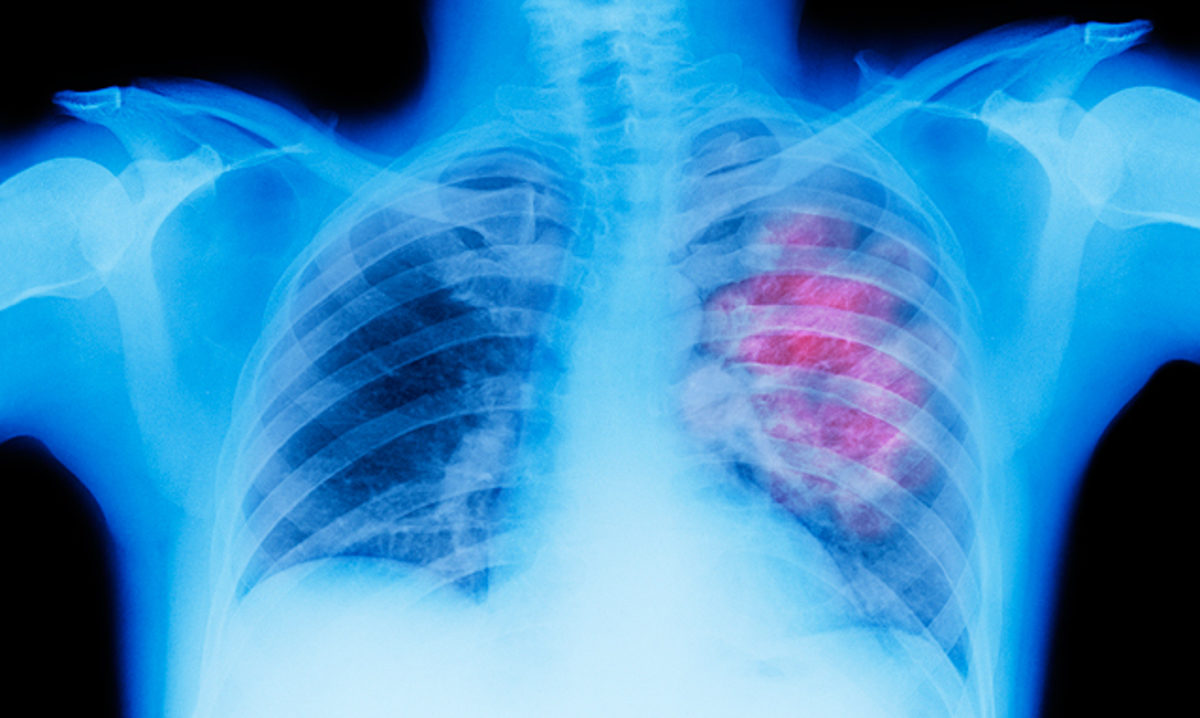

Η επέμβαση περιελάμβανε λοβεκτομή και συστηματικό λεμφαδενικό καθαρισμό σε ασθενή με καρκίνο του αριστερού άνω λοβού πνεύμονος.

Η πρώτη στην Ελλάδα επέμβαση ρομποτικής λοβεκτομής θώρακα, πραγματοποιήθηκε στο Ιατρικό Διαβαλκανικό Θεσσαλονίκηςαπό το Διευθυντή της Θωρακοχειρουργικής Κλινικής, Δρ. Δημήτριο Φιλίππου και την ομάδα του. Για την εφαρμογή της ρομποτικής τεχνικής είχαν συνηγορήσει οι ενδείξεις του προεγχειρητικού ελέγχου, ενώ τα ιστολογικά αποτελέσματα, επιβεβαίωσαν την ορθότητα της απόφασης.